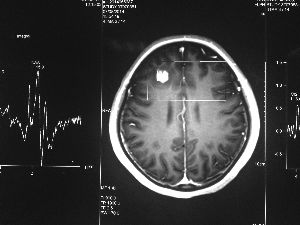

方框亮點為CT片顯示的異物

今年6月份,張敏在宿舍休息時,又發起了癲癇,也是口吐白沫,渾身抽搐。送到蘇州一家大醫院,頭顱核磁共振檢查出,張敏大腦右額葉處有一處病灶,也就是大腦額頭處有個東西。

腦袋里的東西,到底是腫瘤還是其他什么東西,這個謎像個石頭一樣,壓得張敏一家人喘不過氣。7月份,張敏一家又來到南京腦科醫院求醫,第三次檢查后,醫生覺得很像是寄生蟲。不過,影像的檢查,只能作為醫生推測的依據,具體是什么,只有手術拿出來后才能知道。

8月14日,張敏上了手術臺進行開顱手術。術中,楊坤將白色像棉線一樣的異物夾出來后,最初還沒有意識到是什么東西。“放在手術臺上的時候,它竟然動起來了,我當時就想到,這是寄生蟲。”楊坤說,“我們量了一下,蟲子有3厘米長。”